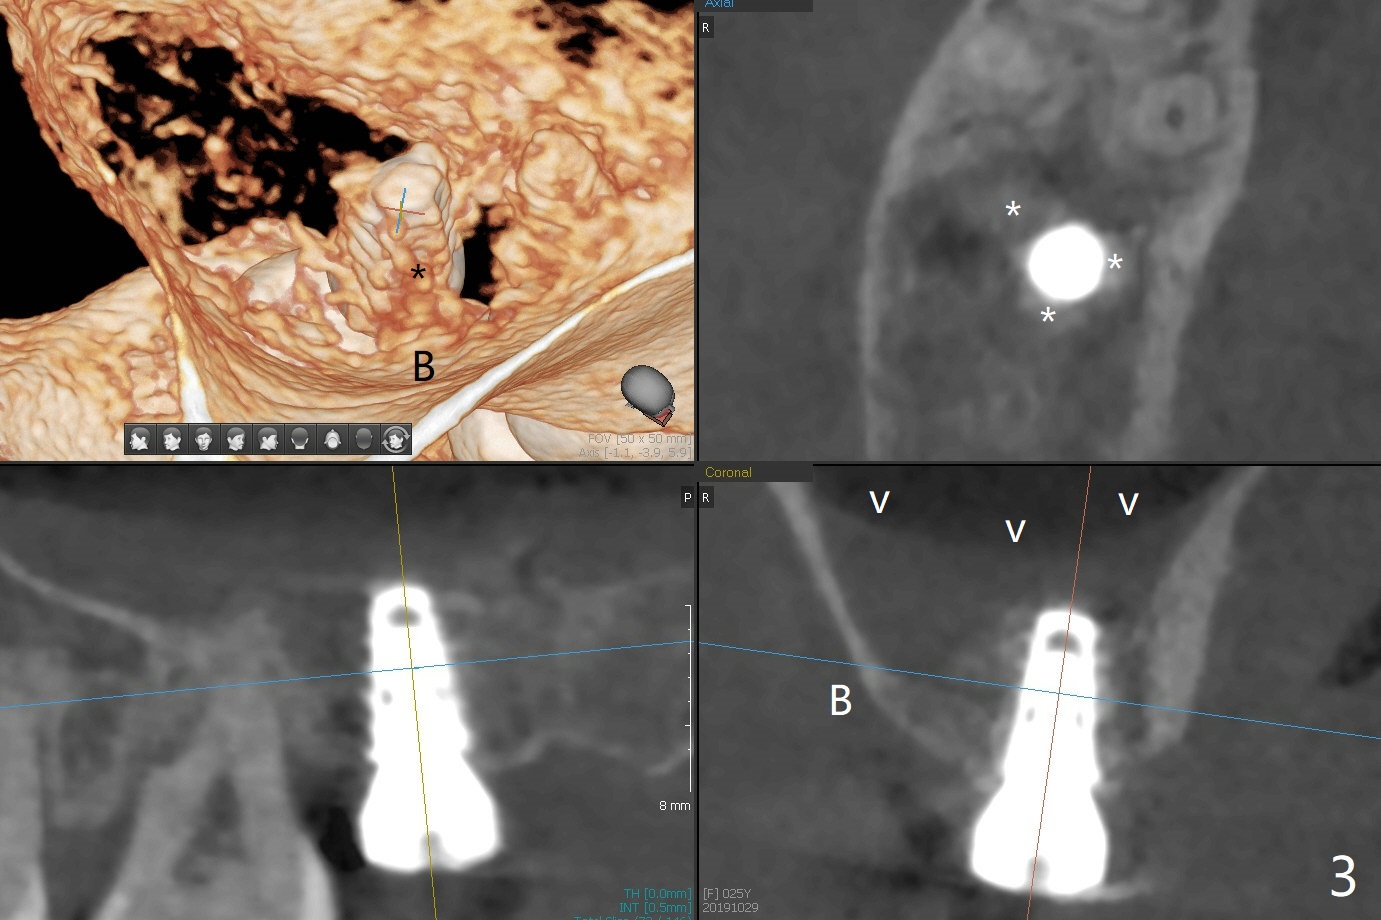

With 4-5 mm remaining bone at #2, the initial osteotomy is 4.0x3.5 mm with regular drills with sharp end. After using 3.6 mm sinus drill with round end for ~ 4 mm in depth, water lifting is conducted smoothly. After use of the same safe drill for ~ 5 mm, water lifting is done. Nose blowing indicates possible sinus membrane perforation. With insertion of collagen plug (PRF is not prepared because of thin vein), mixture of autogenous bone and allograft is lifted with 4x9 mm dummy implant with a guide (Fig.1 G). With placement of more of bone graft, a 4.5x7 mm definitive implant is placed with ~ 25 Ncm (Fig.2). Although bone graft around the implant is limited (Fig.3,4 *), the sinus membrane is lifted (in fact expanded by water) substantially (arrowheads, as compared to preop CT). The healing abutment is dislodged 1 month postop. Before impression, use sensor 1 to take PA to determine whether the abutment contacts the crestal bone or not. Take 5x5 cm CT for sinus membrane thickness. Although the bone graft surrounds the implant 3 months postop, the implant is tender when a 4.5x4(2) mm cemented abutment is being placed (Fig.5). Later a healing screw is placed (Fig.6,7). The sinus membrane has shrunk (arrowheads). Progressive loading is mandatory. The implant is uncovered with a 6x2 mm healing abutment 6.5 months postop (Fig.8). A 5.5x4(2) mm pair abutment is placed and torqued at ~20 Ncm with mild tenderness 7 months postop (Fig.9 BW). A provisional is fabricated for progressive loading because of mild crestal bone loss (*). The abutment is able to be torqued at 35 Ncm 9 months postop. Impression is taken. Return to Upper Molar Immediate Implant Trajectory II 18 Next Case with 3-4 mm Bone Screw Xin Wei, DDS, PhD, MS 1st edition 10/29/2019, last revision 02/23/2021